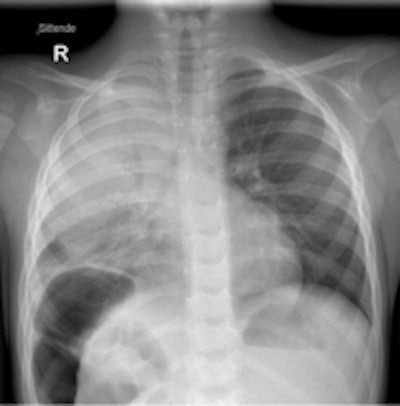

A 1-year-old girl presenting with breathing difficulties after playing with sand. Chest x-ray shows hyperinflation of the left lung and mediastinal shift to the right caused by a check valve mechanism of a small stone (black arrow) visible in the left main bronchus. All images courtesy of Dr. Charlotte de Lange.Chest x-rays and ultrasound exams are most commonly performed to diagnose and monitor treatment of newborns and young infants. Respiratory infections, both bacterial and viral, are the most common. Congenital abnormalities of the airways can cause acute respiratory problems during pulmonary infections. While x-rays are initially recommended, multidetector CT scans with multiplanar reconstructions and volume-rendering are superior in depicting the anatomy.